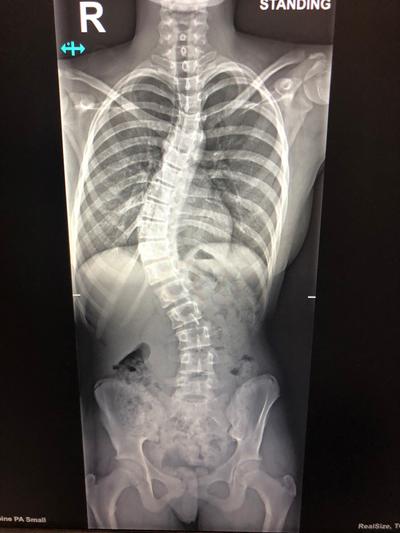

On that first visit, Jonathan Lucas noted the pronounced 53° curvature of Bode’s spine. By the next appointment, the curve had progressed to almost 56°. “It was almost visibly changing, month by month. That’s when Mr Lucas told us that Bode would definitely need surgery,” says Cassie. Bode continues: “He said that without surgery the curve would start to really impact my thoracic and lung capacity in later life and may affect my ability to run around and do sport – which was already a bit diminished. By then I was almost 14 and Mr Lucas said I was already 85% skeletally mature, so bracing wasn’t an option in the way it is if you’re in earlier stages of growth.”

The surgery fitted Bode with one titanium and one cobalt chrome rod on either side of her spine held in place by 18 screws. “Comparing the before and after X-Rays, they managed to make my spine perfectly straight which was incredible."

X-ray.jpg  X-ray 2.jpg